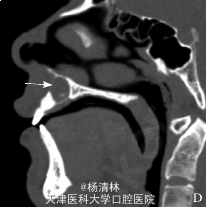

检查:12、11牙间的前庭沟区肿胀、压痛、触及囊性感;肿胀区相关牙未见龋坏、变色及异常松动,牙髓电活力检测试验反应正常。辅查:穿刺细胞学检查:穿刺得脓性囊液,涂片镜检见胆固醇结晶。 CT 示:左、右上中切牙与侧切牙之间根尖平面以上,骨组织内对称性分布的 2 枚多生牙;右侧见低密度囊性影,且多生牙包含其中。

诊断:上颌骨前部骨埋伏阻生多生牙并右侧含牙囊肿。处理:控制伴发的继发性感染后于局麻下行囊肿刮治及骨埋伏阻生牙拔除术,术后 7 d 治愈出院。

手术标本行常规石蜡包埋切片,病理表现为薄层复层鳞状上皮增生,钉突明显,纤维壁内见大量炎细胞浸润,病理诊断为含牙囊肿伴感染。 锥形束 CT 可以对颌骨病变,特别是多生牙的三维定位提供更全面、更准确的诊断依据,清晰地显示阻生牙的唇腭向、颊腭向、垂直向位置关系,并可以测量阻生牙与上颌窦、下颌神经管等重要解剖结构之间的距离,以确保手术安全,同时锥形束 CT 较普通 CT 具有辐射低、空间分辨率高的优点(病例来源于网络)